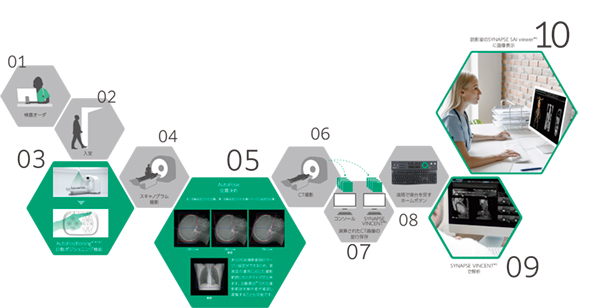

新しいワークフローソリューション SynergyDrive

チーム医療を支え続けてきた富士フイルムだからこそできたAI時代の新しいワークフローソリューション。それがSynergyDriveです。深層学習等のAI技術を活用したワークフロー支援機能により,医療現場の様々な課題を解決し診療の効率化と質の向上に貢献します。